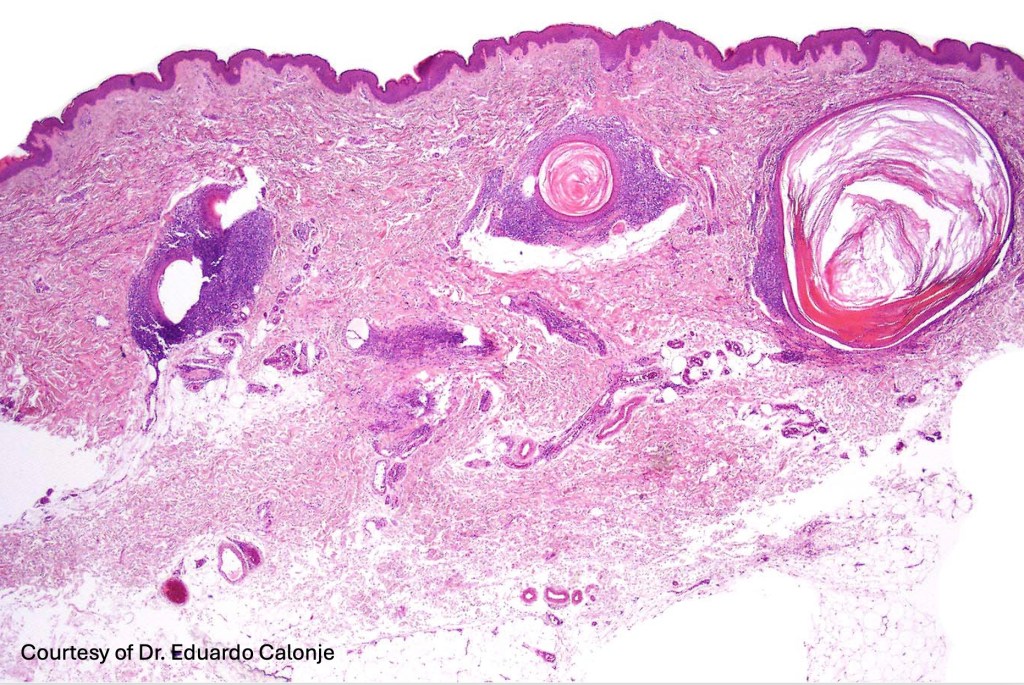

Histological features

•Epidermal involvement often absent

•Follicular infiltration by atypical lymphocytes & Sézary cells

•+/- mucinosis

•+/- basaloid follicular hyperplasia